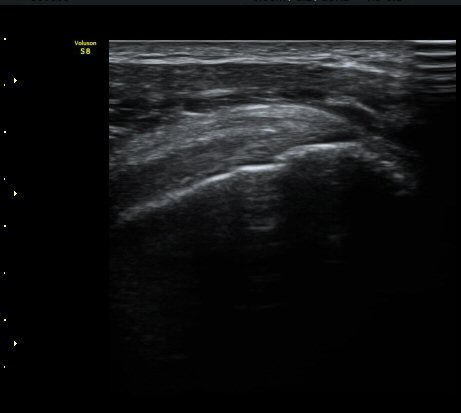

ÃÊÀ½ÆÄ °Ë»ç

ÀÌµÎ¹Ú±Ù°Ç È¾´Ü¸é°Ë»ç¿¡¼­ ƯÀÌ ¼Ò°ßÀ» º¸ÀÌÁö ¾ÊÀ½(»çÁø 1, 2).